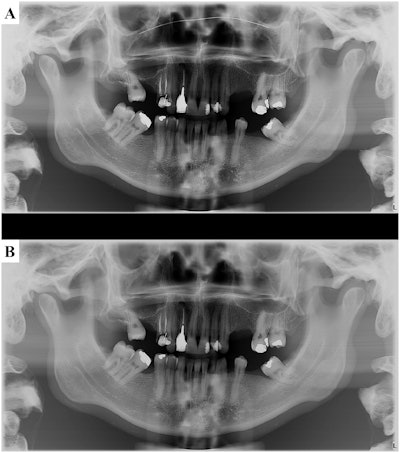

They noted a few pitfalls to their technique, such as artifacts caused by nose wires in the masks, but they ultimately found the quality of imaging is unaffected when masks are worn.

To that end, one factor to note is that most face masks include a nose wire. This can lead to the generation of metal artifacts that decrease image quality during CBCT. Simply remove the wire from the mask before image acquisition to avoid the superposition of its image on the nasal cavity and maxilla, the team suggested.

Imaging professionals should be aware that the effect of the nose wire may vary according to the thickness of the metal, the team wrote.